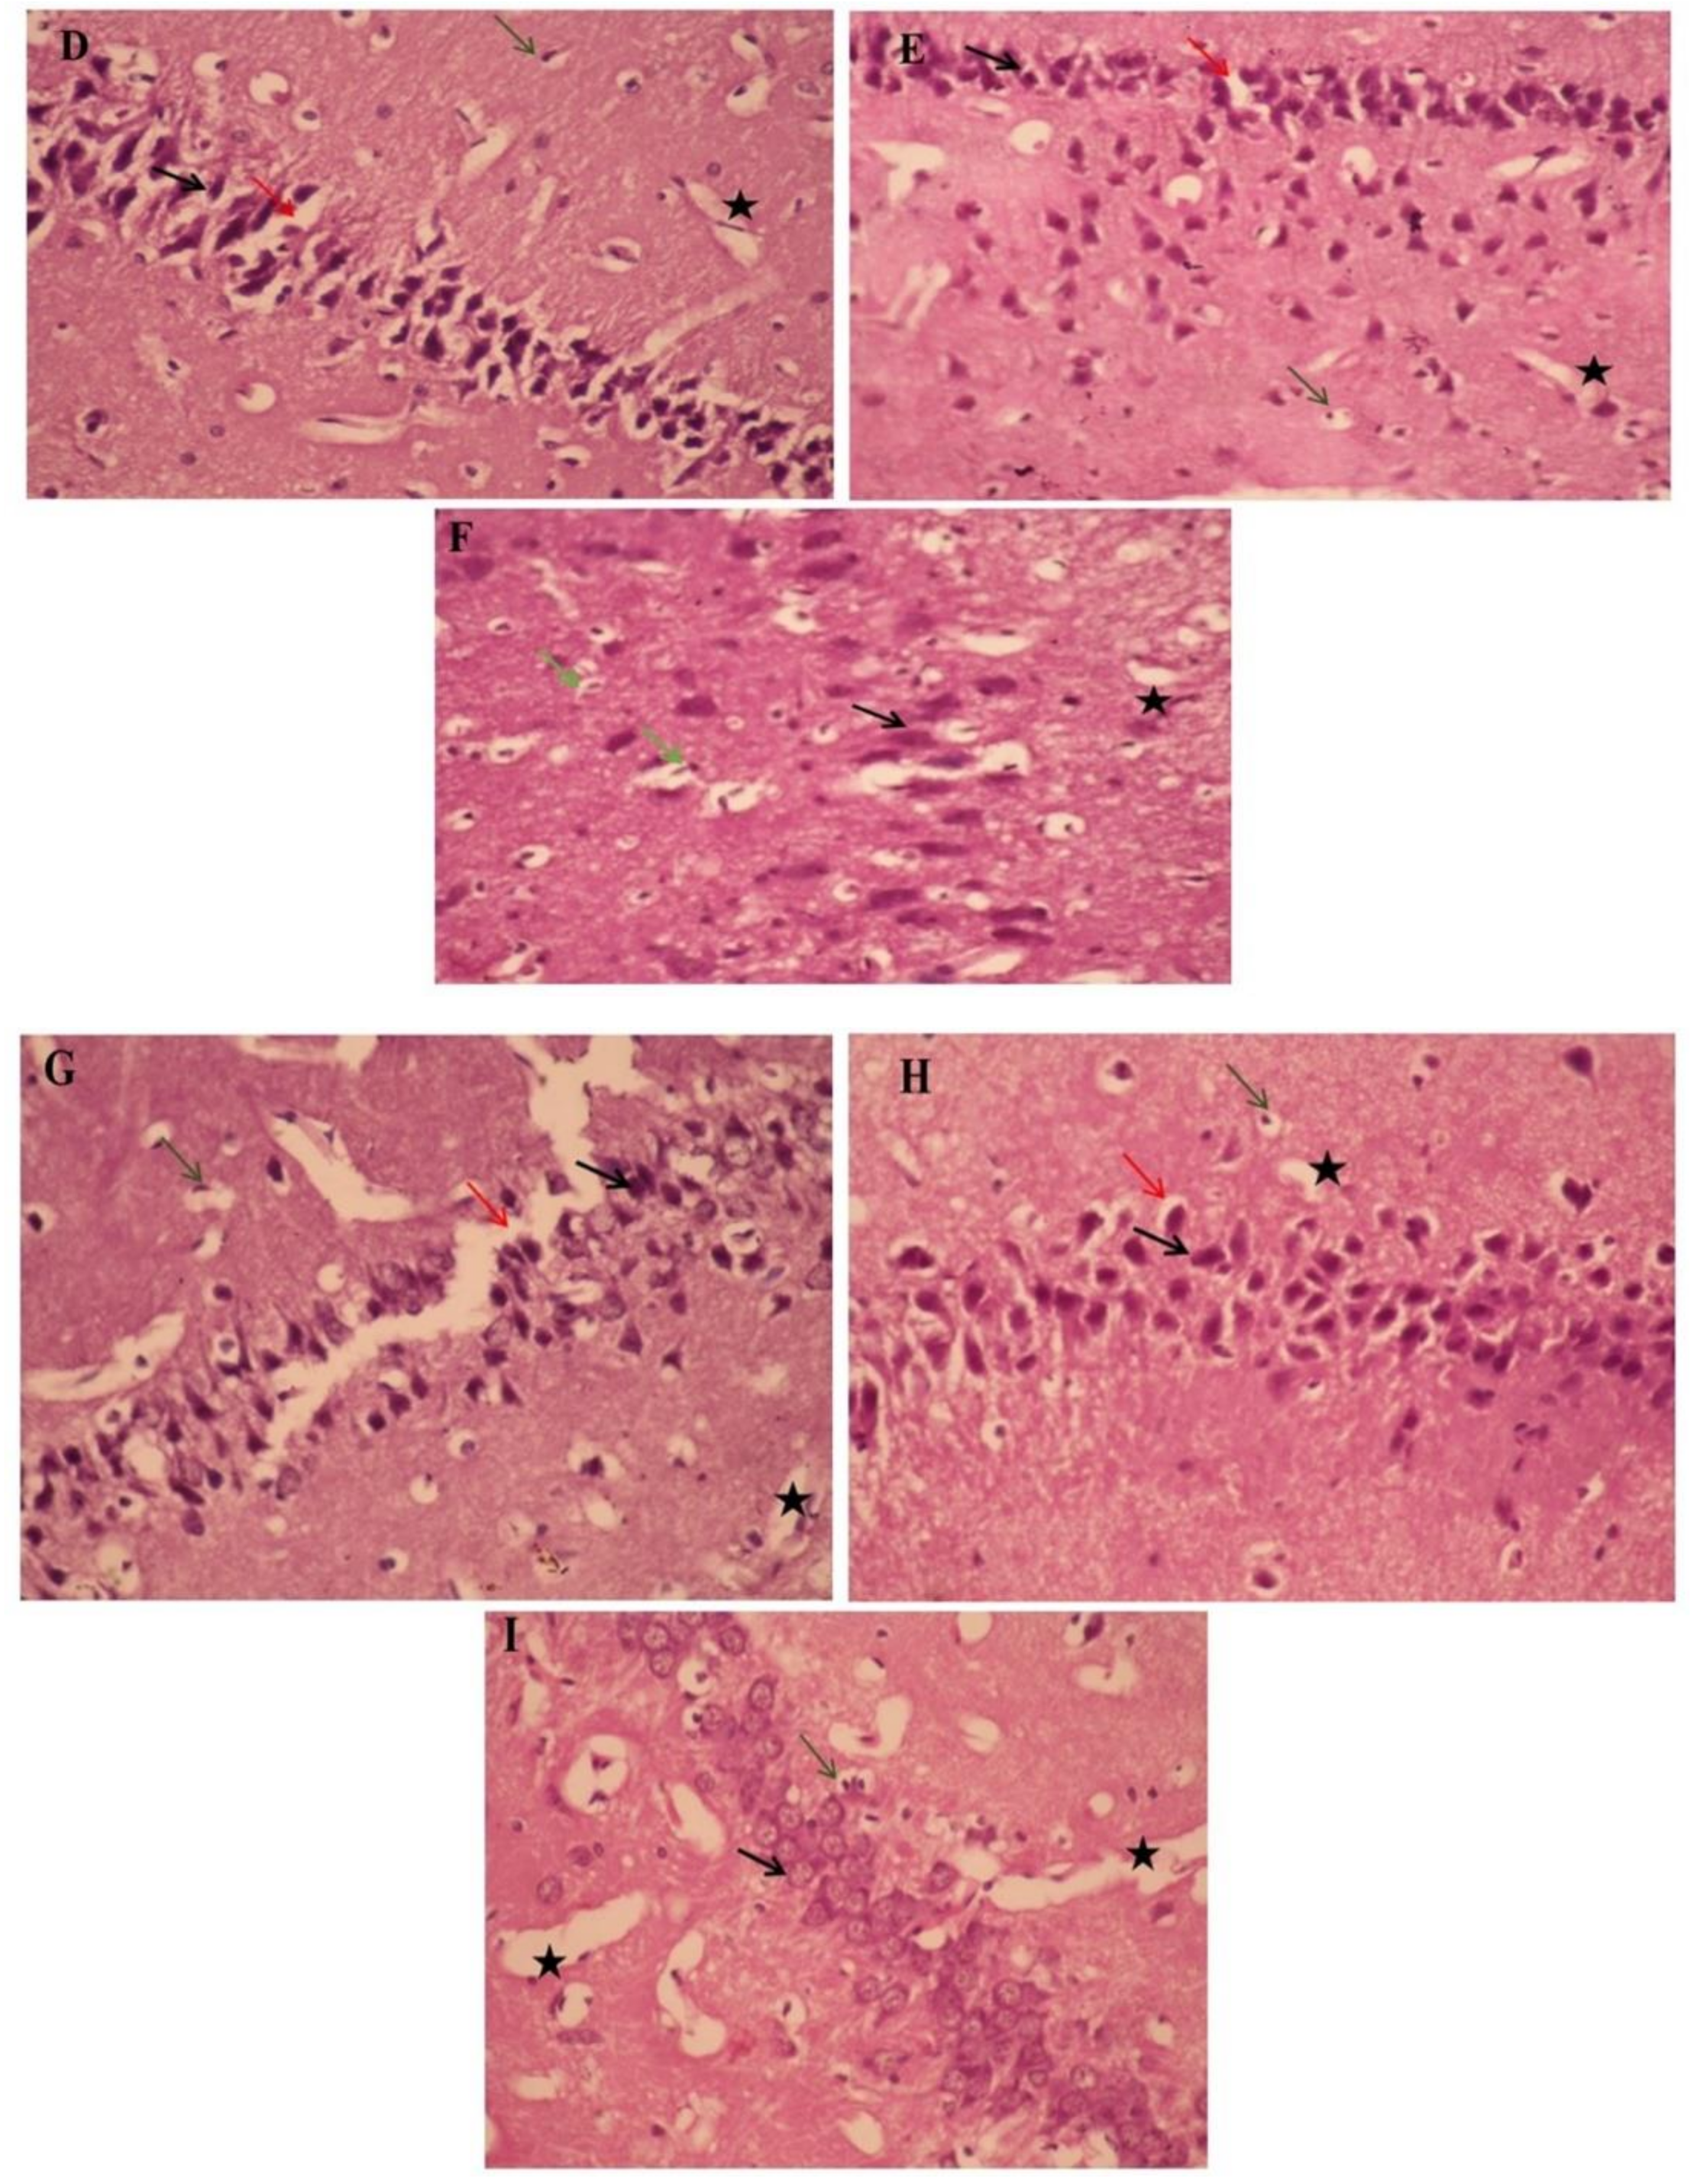

The histopathological study of the hippocampi was seen in Figure 6. Paraffin section photomicrographs of control brains show the hippocampus area with arranged pyramidal cells with large pyramidal nuclei and minimum vacuolated cytoplasm, few pyknotic neuropil cells, and homogenous brain tissue (Figure 6A). Conversely, the H&E-stained sections of type 2 diabetes-induced group display a marked proliferating pyramidal cell forming gland feature and have dark nuclei with minimum vacuolated cytoplasm and many pyknotic neuropil cells, marked congested, dilated blood vessels and capillaries, beside edema and reduction of the myelinated sheath, indicating AD induction (Figure 6B). Moreover, paraffin section photomicrographs of rat brains treated with curcumin-50 show the hippocampus area with some pyramidal cells, hyperchromatic nuclei, and marked vacuolated cytoplasm with many pyknotic pyramidal cell and neuropil cells, as well as reduction of the myelinated sheath, and a mildly dilated and hemorrhaged blood capillary was seen (Figure 6C). Besides, the brain photomicrographs of the induced group treated with CurNP-10 shows the hippocampus region with dark pyramidal nuclei and low vacuolated cytoplasm (normal architecture) and few pyknotic pyramidal cells; few neuroglial cells have rounded nuclei; prominent nucleolus, marked hemorrhage dilated blood vessels, and capillaries with the homogenous field of myelinated sheath and edema were seen (Figure 6D). In addition, the brain photomicrographs of the induced group treated with CurNP-50 show hippocampi with few neuroglial cells and proliferating pyramidal cells, having dark pyramidal nuclei and mild vacuolated cytoplasm. Furthermore, rearrangement of a pyramidal cell for the organized hippocampus region and a few necrotic ones were noticed. A mildly dilated and hemorrhaged blood vessel with homogenous brain tissue was seen (Figure 6E). In addition, rat brains treated with zinc sulfate-50 showed a hippocampus area with some pyramidal cells, hyperchromatic nuclei with homogenous cytoplasm, few necrotic and many pyknotic pyramidals, as well as neuroglial cells. A mildly dilated and hemorrhaged blood capillary with a mildly degenerative myelinated sheath was also seen (Figure 6F). Furthermore, the brain photomicrographs of the ZnONP-10-treated group showed a hippocampus with regenerative pyramidal cells and hyperchromatic nuclei, with mild vacuolated cytoplasm and few necrotic neuroglial cells. A mildly dilated blood capillary with an area of homogenous brain tissue was also seen (Figure 6G). In addition to this, the brain photomicrographs for the ZnONP-50-treated group showed a hippocampus with the normal features of many neuropil cells and few pyknotic ones, and mild proliferating pyramidal cells with hyperchromatic nuclei and mildly vacuolated cytoplasm. A mildly dilated and hemorrhaged blood vessel with homogenous brain tissue was also observed (Figure 6H). The brain photomicrographs of metformin-treated rats showed the hippocampus region with many neuroglial cells with rounded nuclei and a prominent nucleolus, as well as necrotic neuroglial cells. Many necrotic pyramidal cells and others with small nuclei (atrophied pyramidal cells) and pyknotic pyramidal cells were seen. Markedly dilated and hemorrhaged blood vessels and capillaries were also noticed, as was the reduction of a myelinated sheath in the necrotic area (Figure 6I).

The effects of ZnONP and CurNP on the histology of hippocampi in rat groups. Hippocampi of rats were evaluated via hematoxylin-eosin (H&E) staining at 400 X magnification. (A) The control group: a photomicrograph of the hippocampus showing arranged pyramidal cells (black arrows) with minimum vacuolated cytoplasm (Red arrows), a few pyknotic neuropil cells (Green arrows), and homogenous brain tissue (black asterisk). (B) Untreated HFD/STZ-induced group: a photomicrograph of the hippocampus showing marked proliferating pyramidal cells with dark nuclei (black arrows) with minimum vacuolated cytoplasm (red arrows) and many pyknotic neuropile cells (green arrows), and reduction of the myelinated sheath (black asterisk). (C) HFD/STZ-induced rats treated with curcumin: a photomicrograph of the hippocampus showing some pyramidal cells with hyperchromatic nuclei (black arrows) and marked vacuolated cytoplasm (red arrows) and many neuropile cells (green arrows), with mildly dilated and hemorrhaged blood capillaries (black asterisk). (D) HFD/STZ-induced rats treated with CurNP-10: a photomicrograph of the hippocampus showing normal features of many neuropil cells and few pyknotic ones (green arrows), mildly proliferating pyramidal cells with hyperchromatic nuclei (black arrows) and mildly vacuolated cytoplasm (red arrows) with homogenous brain tissue (black asterisk). (E) HFD/STZ-induced rats treated with CurNP-50: a photomicrograph of the hippocampus showing pyramidal cells having dark pyramidal nuclei (black arrows) and mildly vacuolated cytoplasm (red arrows) with few necrotic ones (green arrows) and homogenous brain tissue (black asterisk). (F) HFD/STZ-induced rats treated with zinc sulfate: a photomicrograph of the hippocampus showing some pyramidal cells with hyperchromatic nuclei and homogenous cytoplasm (black arrows), many neuroglial cells (green arrows), with mildly degenerative myelinated sheaths (black asterisk). (G) HFD/STZ-induced rats treated with ZnONP-10: a photomicrograph of the hippocampus showing pyramidal cells, dark pyramidal nuclei (black arrows) and low vacuolated cytoplasm (normal architecture) (red arrows), prominent nucleolus (green arrows), and markedly hemorrhaged dilated blood vessels and edema (black asterisk). (H) HFD/STZ-induced rats treated with ZnONP-50: a photomicrograph of the hippocampus showing hyperchromatic nuclei (black arrows) with mild vacuolated cytoplasm (red arrows), and pyknotic pyramidal (green arrows), with the area of homogenous brain tissue (black asterisk). (I) HFD/STZ-induced rats treated with metformin: a photomicrograph of the hippocampus showing many prominent nucleoli (green arrows), pyknotic pyramidal cells (black arrows), and reduction of myelinated sheaths in the necrotic area (black asterisk).

The damage in any cell in the hippocampus can cause gross effects on the learning process of the individual. After histopathological examination of normal and diabetic hippocampal sections, results revealed that diabetes had a significant effect in the form of cell death in various areas, as well as disruption of normal layer organization. This was associated with clumping of neuronal processes, a sign of neuronal injury [89]. Fortunately, these changes were significantly improved by the administration of CurNP and ZnONP, showing well-preserved pyramidal cells in both groups, which confirms the neuroprotective effect of both nanoparticles on brain cells through the improvement of neurogenesis.